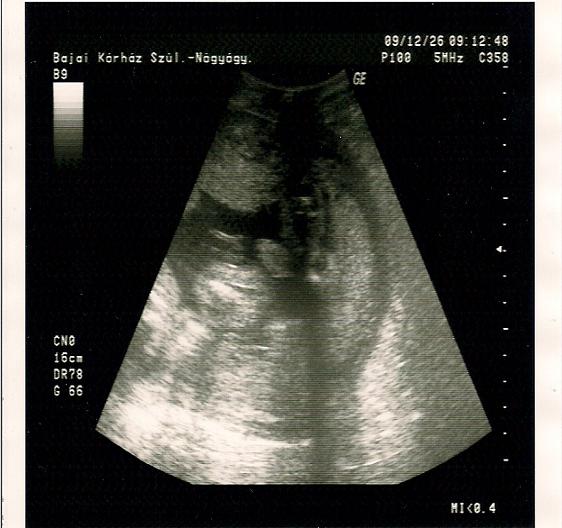

Talalkoztal ma Jolival a korhazban?...Drukkolok a köv heti UH miatt!!